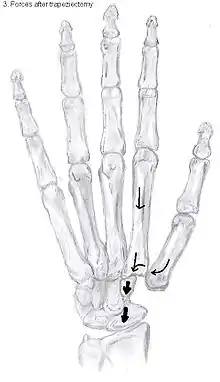

Trapeziectomy

During trapeziectomy,[30] the trapezium bone is removed without any further surgical adjustments.The trapezium bone is removed through an approximately three centimeter long incision along the lateral side of the thumb. To preserve surrounding structures, the trapezium bone is removed "by splitting" it into pieces.

An empty gap is left by the trapeziectomy and the wound is closed with sutures. Despite this gap, no significant changes in function of the thumb are reported.[27] After the surgery, the thumb will be immobilized with a cast.

Trapeziectomy with Tendon Interposition

Some physicians still believe that it is better to fill the gap left by the trapeziectomy. They assume that filling the gap with a part of a tendon is preferable in terms of function, stability and position of the thumb. This is based on the assumption that interposition can help maintain the space between the metacarpal and the scaphoid, which will improve comfort and capability. Neither of these assumptions is supported by experimental evidence.

During trapeziectomy with TI, a longitudinal strip of the palmaris longus tendon is collected. [31] If this tendon is absent (which is the case in 13% of the population), half of the flexor carpi radialis tendon (FCR) can be used.

The tendon is then formed into a circular shape and placed in the gap, where it is stabilized by sutures.[12]

Trapeziectomy with Ligament Reconstruction

Another technique is used to reconstruct the volar beak ligament after trapeziectomy. The rationale is that ligament reconstruction(LR) helps maintain the gap between the metacarpal and the scaphoid, and that a larger gap is associated with greater comfort and capability.[32] Again these possibilities are not supported by experimental evidence.

During this procedure the anterior oblique ligament is reconstructed using the FCR tendon. There is a wide variety in techniques to perform this LR, but they all have a similar goal.

Trapeziectomy with LRTI

Some physicians believe that combining LR with TI will help maintain gap between the metacarpal and the scaphoid.[33] And that doing so will improve comfort and capability. Keep in mind that these aspects of the rationale are not supported by experimental evidence. The evidence suggests that all of these procedures have comparable long-term results.